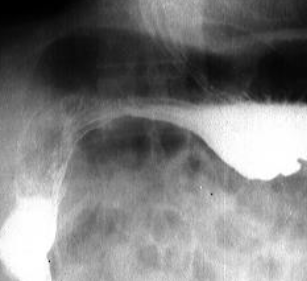

Ulcer gastric